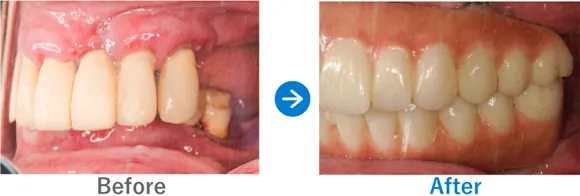

Case2

上下義歯の状態からインプラント治療後に自信を取り戻された方

上下義歯(入れ歯)ほとんど歯が残っていない、残存歯は上顎1本下顎5本のみ。

上顎骨がやせていて普通にはインプラントが出来ない状態。

上顎ザイゴマインプラントでALLON4、下顎ALLON4

10,703,000円(上顎7,128,000円、下顎3,575,000円/内訳:上顎オールオン4(ノーベルザイゴマインプラント4本)、下顎オールオン4(ストローマンインプラント4本)、3Dモデルガイド*、仮歯、セデーション、ボツリヌストキシン注射、3D模型、保証10年)

来院の背景

60代前半から現在の義歯を使っている。初めはピッタリだったが、だんだんと義歯がゆるくなり、鈎歯(こうし)が折れた。歯がダメになったら、インプラントを検討しようと思っていた。ご主人のご友人がインプラントをしたため興味を持ったが、金額もかかるため、家族には相談せずに来院された。

治療結果

上顎ザイゴマインプラント4本。下顎ALLON4で行った。治療完了後、現在もメンテナンスで来院中で経過良好。口元が綺麗になり、お化粧をするなど美意識が高まり、おしゃれに気をつかうようになったとのこと。「笑顔が増えて、よく外出するようになりました。自信がつきました。」